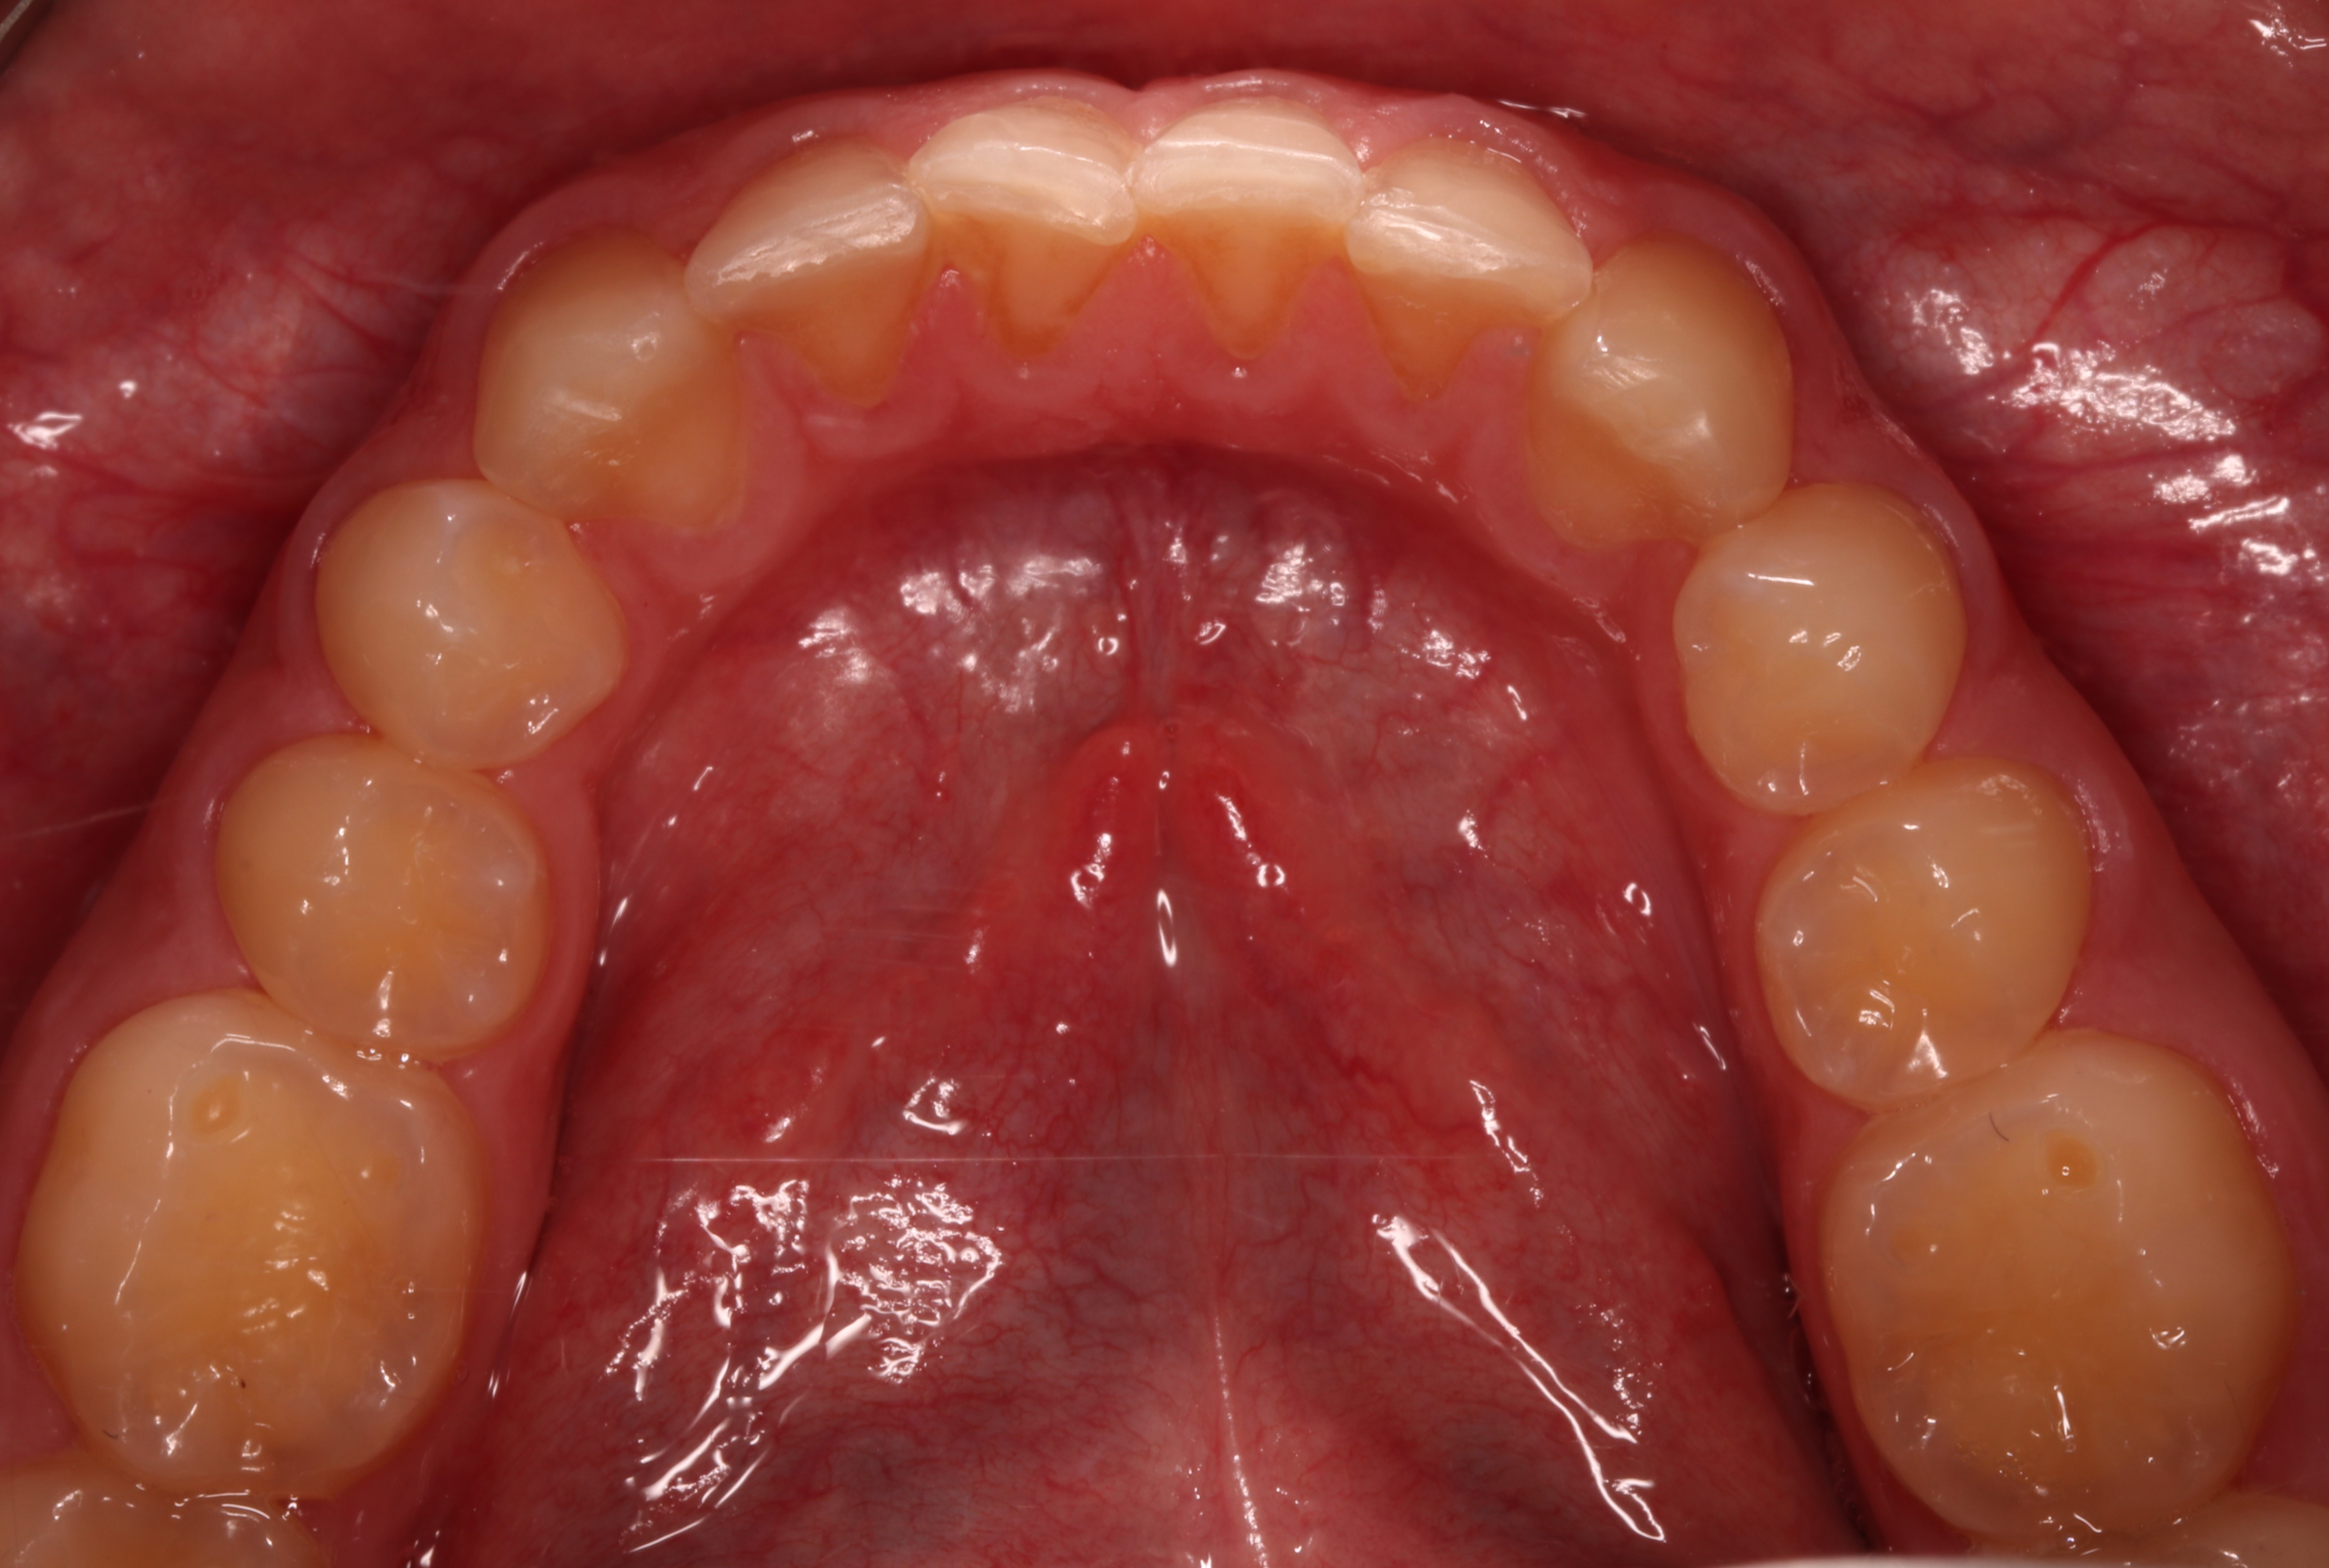

Pacjent, 18 lat, został skierowany w celu leczenia zachowawczego przed planowanym leczeniem ortodontycznym i odbudową startych zębów. W badaniu klinicznym stwierdzono niedostateczną higienę jamy ustnej – osad i złogi miękkie w przestrzeniach międzyzębowych, uogólnioną erozję szkliwa, starcie oraz liczne ogniska próchnicy pierwotnej zlokalizowane na powierzchniach stycznych zębów bocznych (ryc. 1‑4).

Ryc. 3. Sytuacja początkowa – łuk górny.